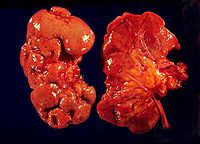

急性肾盂肾炎 病变可为单侧或双侧,局限或广泛,可轻可重,轻者仅累及肾盂粘膜。重者肾脏肿大,切面可见粘膜充血溃疡,小脓肿形成。如伴梗阻,则肾盏增宽,少数严重患者,其肾乳头及锥体部可见坏死,坏死组织随尿液排出称坏死性乳头炎,镜下可见肾间质水肿,嗜中性粒细胞浸润。

慢性肾盂肾炎 肾盂及肾盏有慢性炎症表现。肾盂扩大、畸形,肾皮质及乳头部有瘢痕形成,肾脏较正常缩小,两侧病变常不对称,肾髓质变形,肾盂肾盏粘膜及输尿管管壁增蚅,严重者肾实质广泛萎缩。